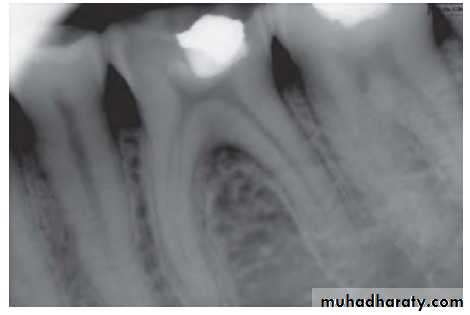

4. Radiographs

3. Radiographs: These show normal PDL and lamina dura.– Depth of caries or restoration may be evident.

Visual examination and history: Examination of involved tooth may reveal previous symptoms. On inspection, one may see deep cavity involving pulp or secondary caries under restorations.2. Radiographic findings:

– May show depth and extent of caries.– Periapical area shows normal appearance but a slight widening may be evident in advanced stages of pulpitis.